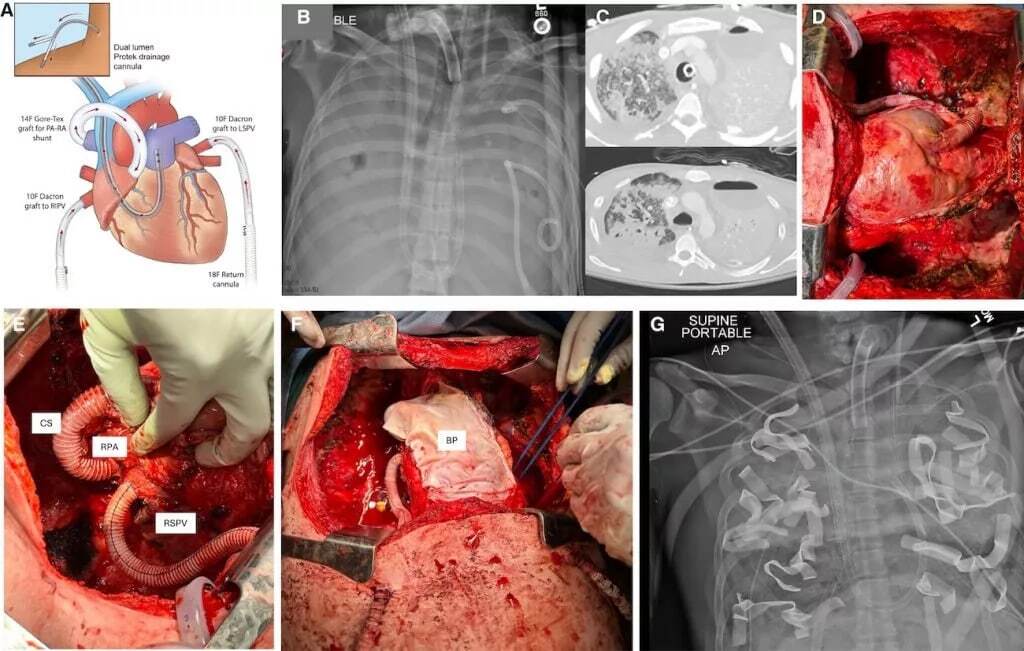

بر اساس گزارش ScienceAlert، پزشکان با ساخت یک سیستم کامل ریه مصنوعی (TAL) توانستند وظیفه تامین اکسیژن خون را دقیقاً مانند ریه های طبیعی انجام دهند. این دستگاه علاوه بر تامین اکسیژن، جریان خون را مدیریت کرده و از قلب محافظت می کند.

برداشتن هر دو ریه معمولاً به دلیل اختلال شدید جریان خون باعث نارسایی قلبی می شود. برای جلوگیری از این اتفاق، تیم پزشکی کانالهای جریان خون دوگانه و یک شنت را برای صاف کردن نوسانات جریان خون در طراحی سیستم TAL اضافه کردند. این دستگاه توانست بیمار را زنده نگه دارد تا بدن او پس از حذف منبع عفونت بهبود یابد و برای دریافت پیوند آماده شود. پس از برداشتن اندام های عفونی، بدن بیمار بلافاصله علائم بهبودی عفونت را نشان داد.